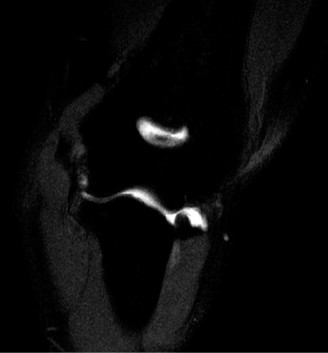

- Magnetic Resonance Imaging (MRI): MRI, preferably with an arthrogram, is the gold standard for evaluating UCL integrity, flexor-pronator pathology, and associated intra-articular injuries (e.g., osteochondral lesions). A complete rupture will show discontinuity of the ligament, while a partial tear may show high signal intensity within the substance of the ligament. T2-weighted fat-saturated sequences are particularly useful.